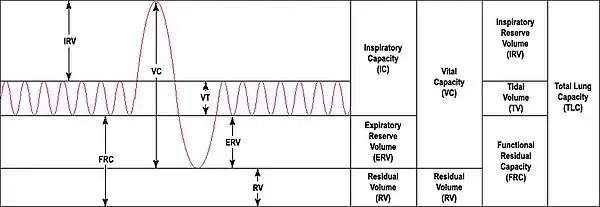

The lungs are not capable of expanding to breathe on their own, and will only do so when there is an increase in the volume of the thoracic cavity.[71] This is achieved by the muscles of respiration, through the contraction of the diaphragm, and the intercostal muscles which pull the rib cage upwards as shown in the diagram.[72] During breathing out the muscles relax, returning the lungs to their resting position.[73] At this point the lungs contain the functional residual capacity (FRC) of air, which, in the adult human, has a volume of about 2.5–3.0 litres.[73]

During heavy breathing as in exertion, a large number of accessory muscles in the neck and abdomen are recruited, that during exhalation pull the ribcage down, decreasing the volume of the thoracic cavity.[73] The FRC is now decreased, but since the lungs cannot be emptied completely there is still about a litre of residual air left.[73] Lung function testing is carried out to evaluate lung volumes and capacities.

Function testing

Lung function testing is carried out by evaluating a person's capacity to inhale and exhale in different circumstances.[101] The volume of air inhaled and exhaled by a person at rest is the tidal volume (normally 500–750 mL); the inspiratory reserve volume and expiratory reserve volume are the additional amounts a person is able to forcibly inhale and exhale respectively. The summed total of forced inspiration and expiration is a person's vital capacity. Not all air is expelled from the lungs even after a forced breath out; the remainder of the air is called the residual volume. Together these terms are referred to as lung volumes.[101]

Pulmonary plethysmographs are used to measure functional residual capacity.[102] Functional residual capacity cannot be measured by tests that rely on breathing out, as a person is only able to breathe a maximum of 80% of their total functional capacity.[103] The total lung capacity depends on the person's age, height, weight, and sex, and normally ranges between four and six litres.[101] Females tend to have a 20–25% lower capacity than males. Tall people tend to have a larger total lung capacity than shorter people. Smokers have a lower capacity than nonsmokers. Thinner persons tend to have a larger capacity. Lung capacity can be increased by physical training as much as 40% but the effect may be modified by exposure to air pollution.[103][104]

Other lung function tests include spirometry, measuring the amount (volume) and flow of air that can be inhaled and exhaled. The maximum volume of breath that can be exhaled is called the vital capacity. In particular, how much a person is able to exhale in one second (called forced expiratory volume (FEV1)) as a proportion of how much they are able to exhale in total (FEV). This ratio, the FEV1/FEV ratio, is important to distinguish whether a lung disease is restrictive or obstructive.[74][101] Another test is that of the lung's diffusing capacity – this is a measure of the transfer of gas from air to the blood in the lung capillaries.